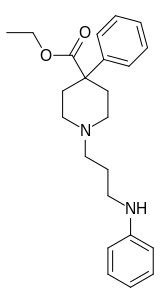

The first fully synthetic opioid was meperidine (later demerol), found serendipitously by German chemist Otto Eisleb (or Eislib) at IG Farben in 1932.[228] Meperidine was the first opiate to have a structure unrelated to morphine, but with opiate-like properties.[199] Its analgesic effects were discovered by Otto Schaumann in 1939.[228] Gustav Ehrhart and Max Bockmühl, also at IG Farben, built on the work of Eisleb and Schaumann. They developed "Hoechst 10820" (later methadone) around 1937.[230] In 1959 the Belgian physician Paul Janssen developed fentanyl, a synthetic drug with 30 to 50 times the potency of heroin.[211][231] Nearly 150 synthetic opioids are now known.[228]

Phenylpiperidines

- Pethidine (meperidine)